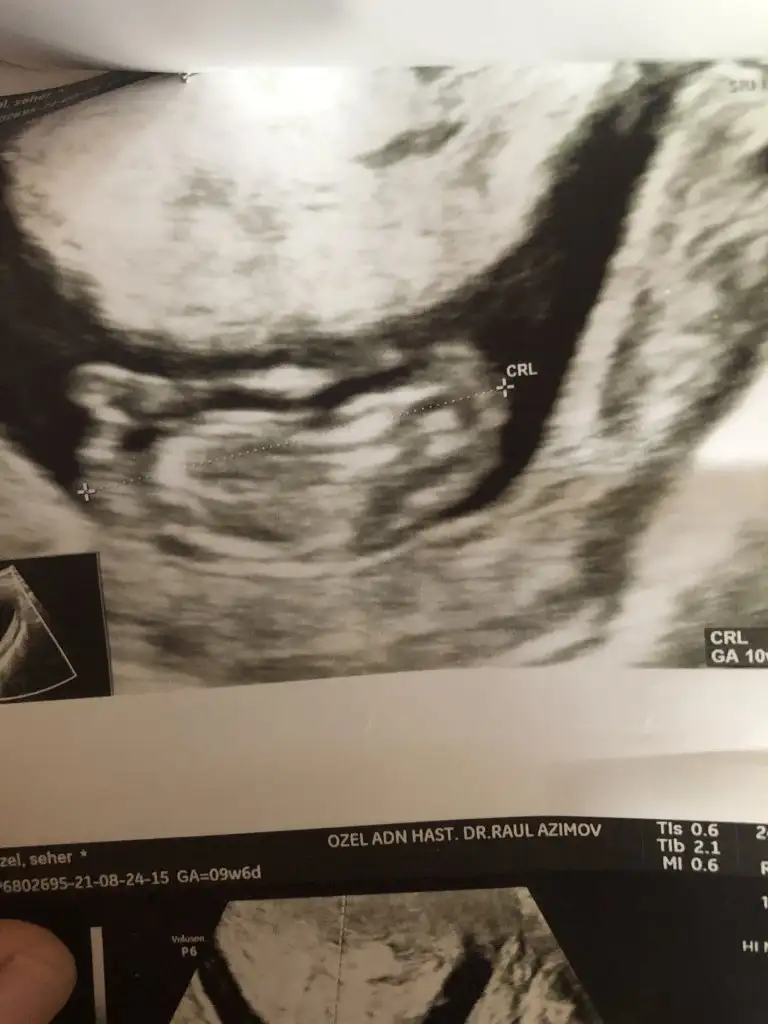

12 haftalık doktor kız gibi dedi ama yanılma çok oluyor dedi 1 ay sonra netleştirirz dedi bazen pipilerini göremiyoruz dedi çok ufak olduğu için yanılabilriz dedi

Ikra meyra merhaba öncelikle benim bebeğimin cinsiyetini doğru tahmin ettiniz teşekkürler rica etsem arkadasımınkine de bakar mısınız